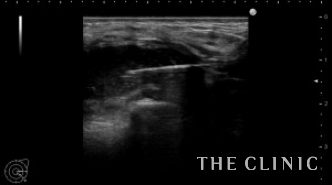

今回は局所麻酔でヒアルロン酸を溶解除去しました。

ほとんど吸引できました。